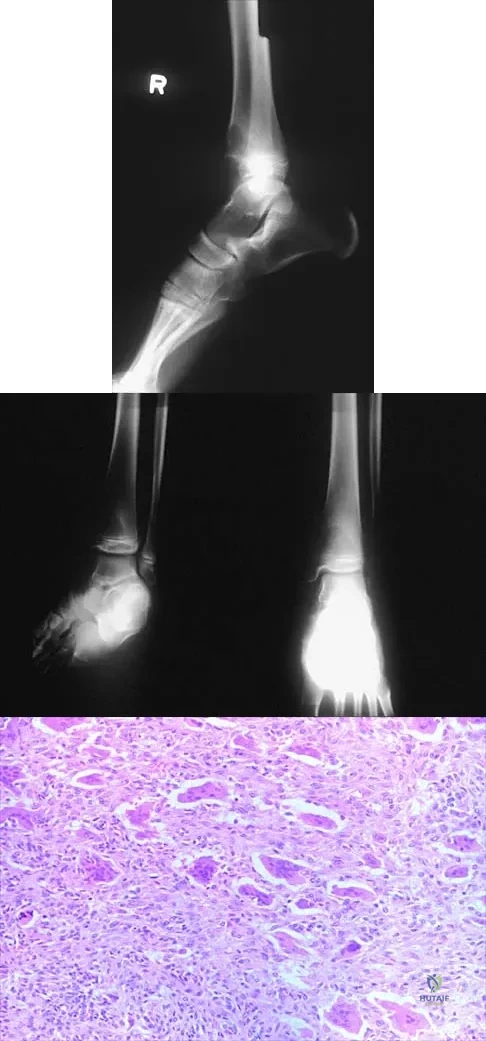

Question 19

A 26-year-old rugby player injured his foot when tackled from behind. Radiographs are seen in Figures 35a through 35c. What is the most appropriate treatment?

Explanation

Question 99

Figures 52a and 52b show the plain radiographs of a 12-year-old girl who has right distal leg pain. She reports that symptoms are present with weight-bearing activities and improve with rest. Examination reveals diffuse tenderness over the distal tibial metaphysis and mild swelling. A photomicrograph of the biopsy specimen is shown in Figure 52c. What is the most likely diagnosis?

Explanation